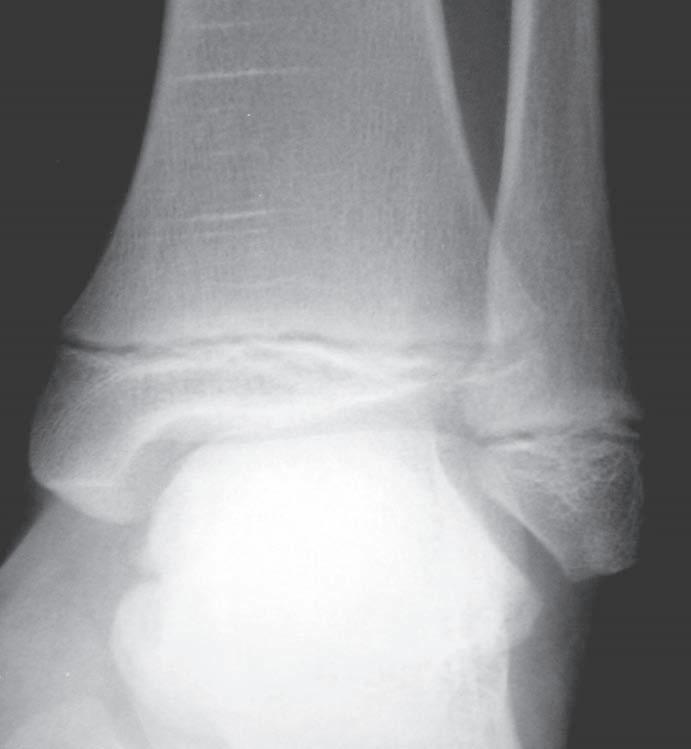

O br. 1. 2 S k iagram hl ezna v pře d oza d ní proje k ci (a) – d is k rétní z d vojení k ontury mediálního kotníku (viz šipka), jinak zdánlivě normální nález; skiagram hlezna v boční projekci (b) – fraktura zadní hrany tibie a zadní části vnitřního kotníku, subluxační postavení v talokrurálním kloubu (viz šipka) ab

P ouze jedna projekce ke správnému vy h odnocení diagnostické informace nes tačí (obr. 1.1). Jde totiž jen o dvojrozměrn ý obraz trojrozměrného objektu, RTG obraz je ted y sumační. Snímkování anatomick ý ch struktur ve dvou na s ebe kolmýc h projekcíc h poskytuje informaci o prostorovém uložení zobrazov an ý ch struktur. Druhá projekce může zobrazit patolo g ick ý proces, kter ý není v iditeln ý v první projekci (obr. 1.2). K dostatečnému zobrazení někter ý ch anatomickýc h struktur (např. člunková kost, C-T h přec h od) je někdy nutné d op l n i t i spec i á l ní pro j e k ce (v i z j e d not li vé k ap i to ly ) .